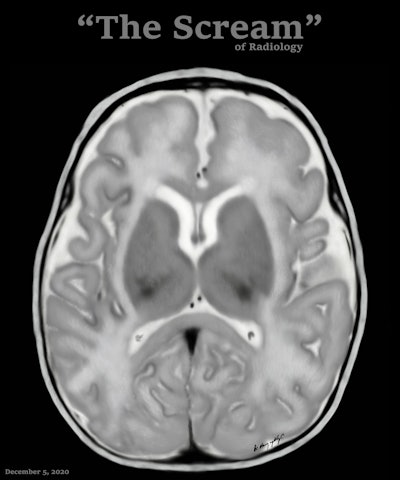

Art and radiology may seem like very different fields, but they can intersect in intriguing ways, particularly in medical imaging and the visualization of complex clinical data. Dr. Harun Yildiz has a keen interest in pediatric radiology, including ultrasound. All images provided by Dr. Harun Yildiz.

Dr. Harun Yildiz has a keen interest in pediatric radiology, including ultrasound. All images provided by Dr. Harun Yildiz.

Conceptually, I think it is possible to define the term “radiological illustration” as an emerging discipline that transforms medical imaging data into an aesthetic and didactic narrative. I emphasize that with the motto “pixel by pixel handmade.” I am trying to open a “new path” for the use of visual communication in medical education by trying to combine scientific accuracy in radiological terms with artistic creativity. With this statement, I am trying to express that instead of modifying radiological images, I draw each pixel by hand using technological tools and create a new visual that is both artistically and scientifically original, while remaining faithful to radiological principles.

It’s important to note that radiological illustration should not be confused with medical illustration. The former has yet to be systematically defined in the literature. I believe it deserves recognition as a distinct sub-branch within the broader medical illustration domain.